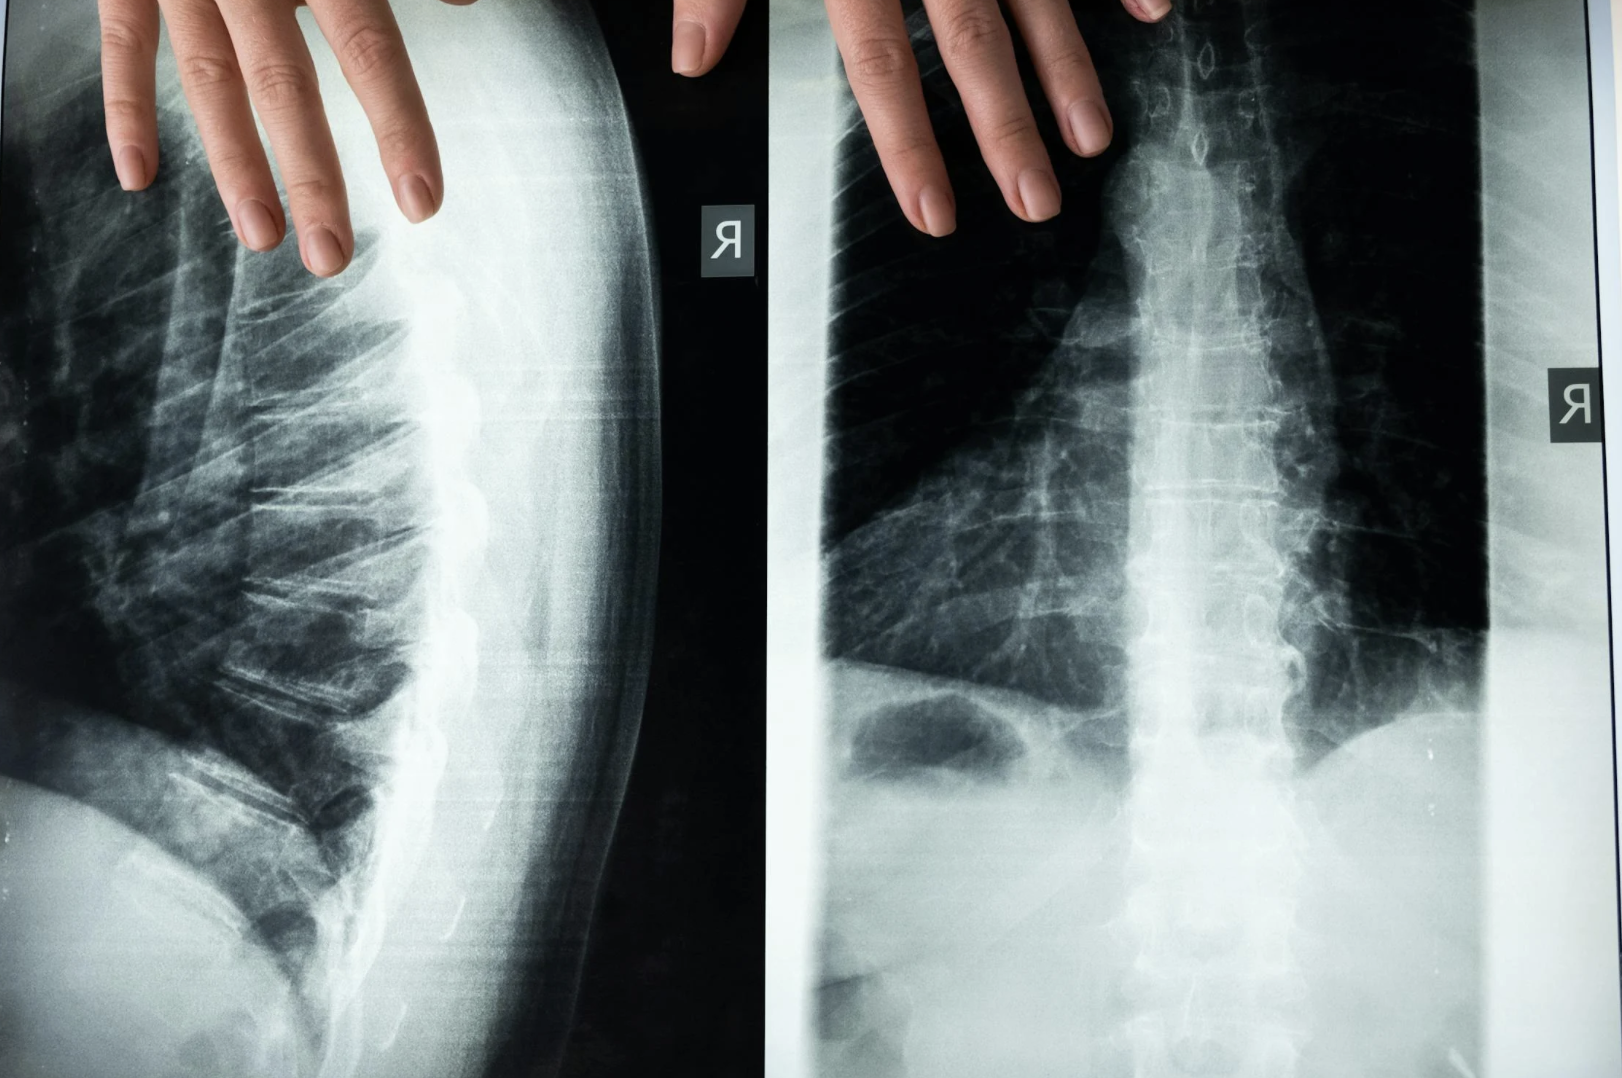

허리통증의 원인과 증상, 허리통증 관리 방법

현대인들이 가장 흔히 겪고 있는 증상인 허리통증은 일상생활에 큰 영향을 미칠 수 있기 때문에 적절한 관리가 중요합니다.

이 글에서는 허리통증의 원인과 증상, 허리통증을 관리하는 방법을 다루어 보겠습니다.